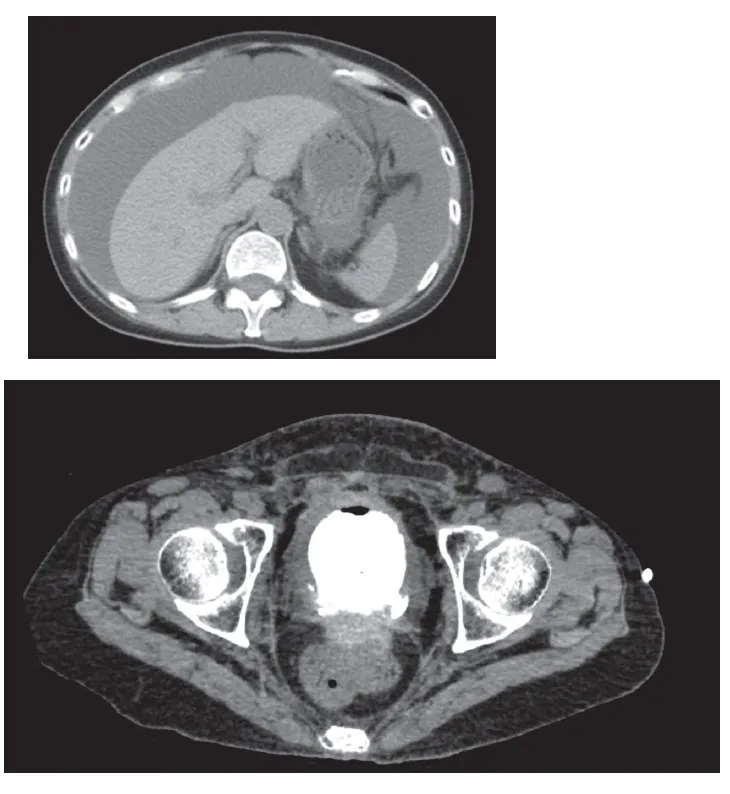

Pseudo-IRA em uma paciente com Ascite